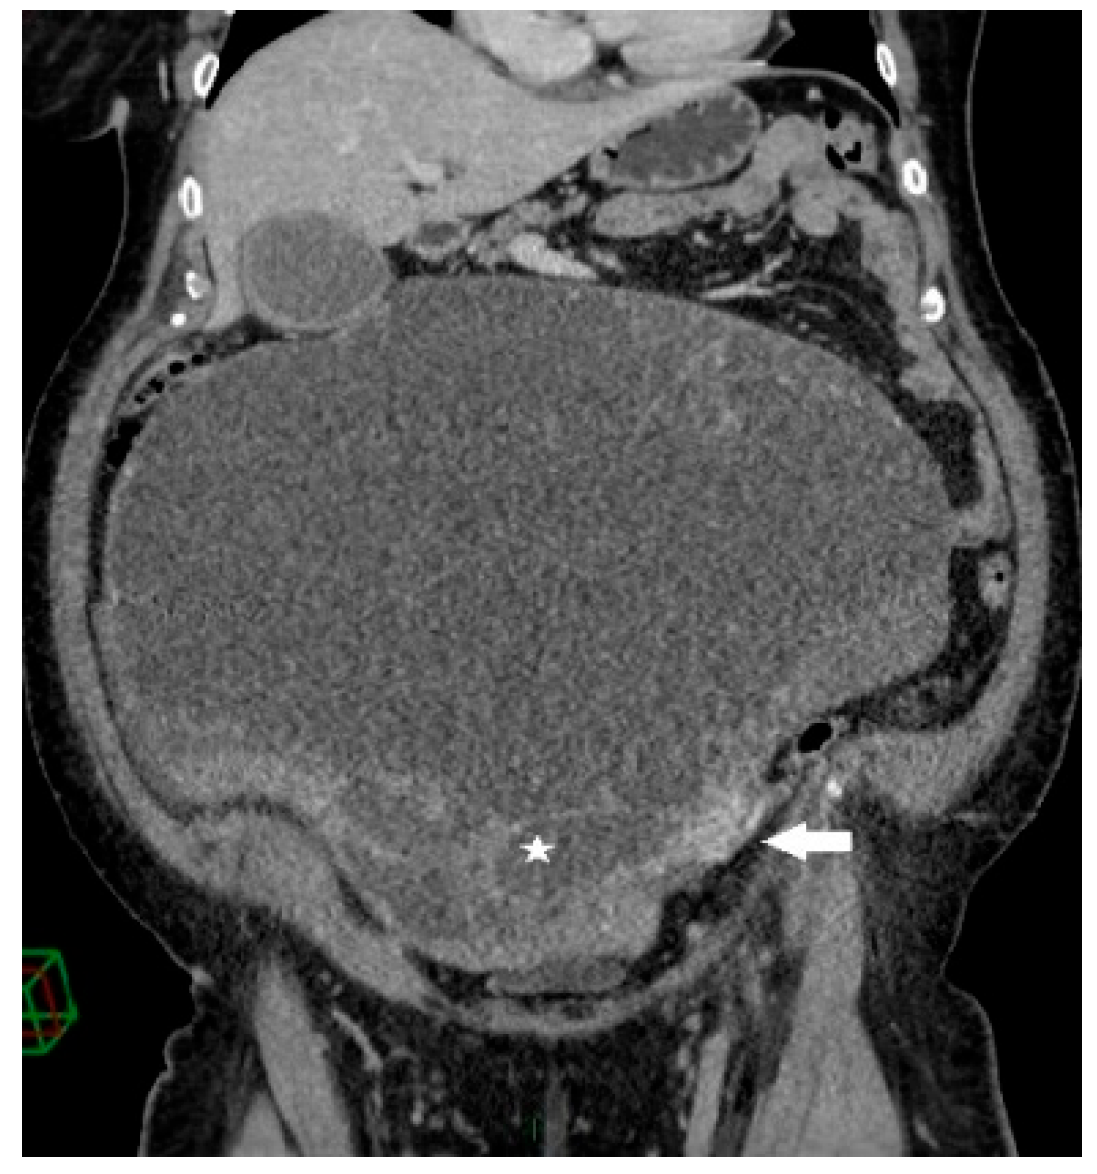

Figure 2.

Coronal contrast-enhanced CT image shows a giant predominantly cystic mass with innumerable tiny locules (white star) of variable attenuation arising from the left ovary, which is surrounded by dilated periovarian veins (white arrow).